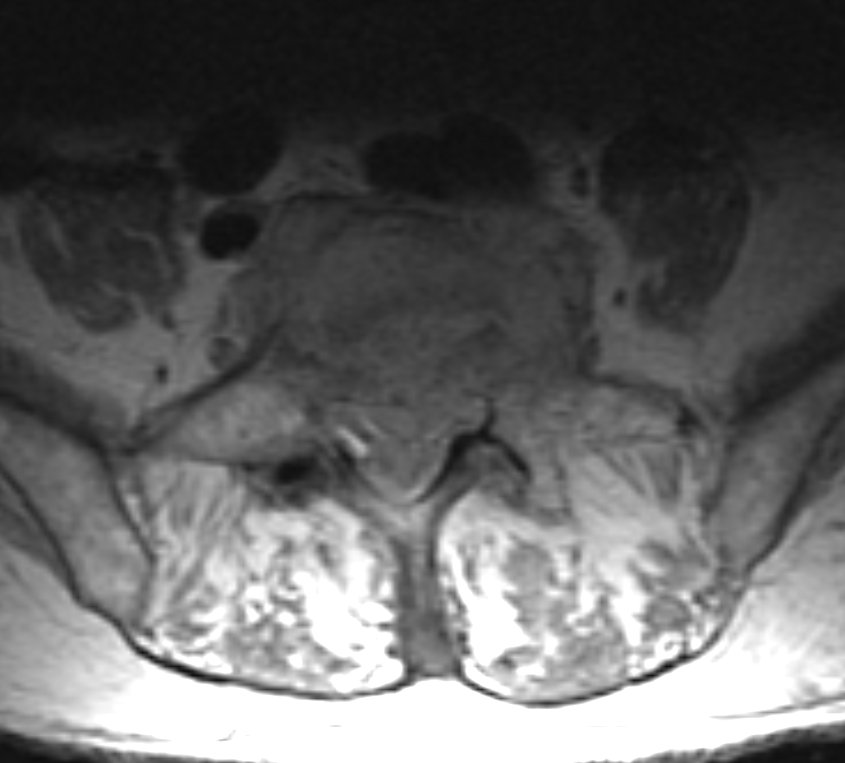

#CaseOfTheWeek ‼️🥳‼️ ☢️🩻☠️Case#37☠️🩻☢️ #BackPain ➡️➡️📲#Diagnosis❓❔❓🎒 #FOAMrad #RadEd #OrthoTwitter SSR_RWG @UWRadRes #MedEd #OrthoSpine NASS

#CaseOfTheWeek ‼️🥳‼️

☢️🩻☠️Case#37☠️🩻☢️

#BackPain

➡️➡️📲#Diagnosis❓❔❓🎒

#FOAMrad #RadEd #OrthoTwitter <a href="/ssr_rwg/">SSR_RWG</a> @UWRadRes #MedEd #OrthoSpine <a href="/NASSspine/">NASS</a>